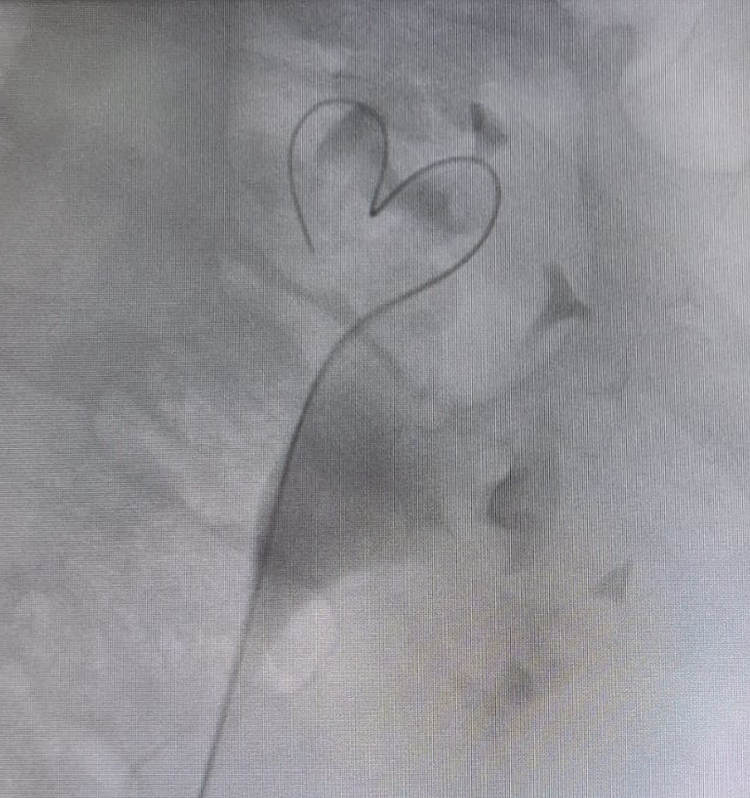

Complete fragmentation of a distal ureteral stone by #ESWL. Radiological and Ultrasound verification. Small stones are also fun!! @FPuigvert @oangerri @koey_kana @paoloverri05 @a_bravo_balado @joanfundi